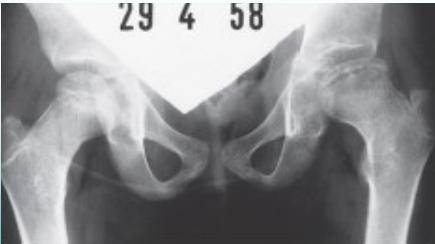

Radiographic Stages:

-

Initial/ Bone Death Stage (Sclerosis)

- May initially appear normal on x-ray

- Increased density followed by collapse

Revascularization and Repair Stage

- Reduced density and fragmentation on x-ray

Distortion and Remodeling Stage

- Distortion, flattening (coxa plana)

- Enlargement (coxa magna) with partial uncoverage

Radiological Progression:

Progression: Sclerosis → Collapse → Fragmentation → Remodeling

Imaging Examples: